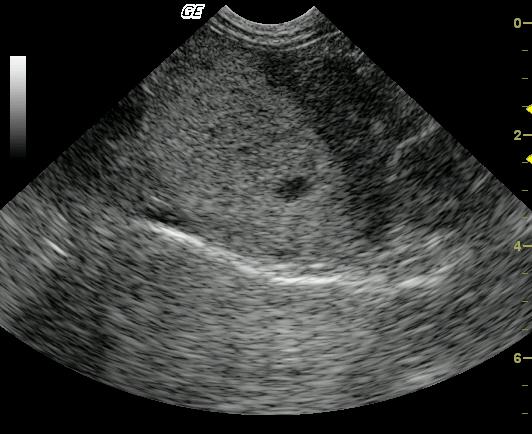

A 9-year-old FS DLH cat was presented with anorexia. Physical examination revealed mild dehydration and poor body condition. Mildly elevated SAP and mildly elevated ALT were found in the blood chemistry profile. Urinalysis was unremarkable.